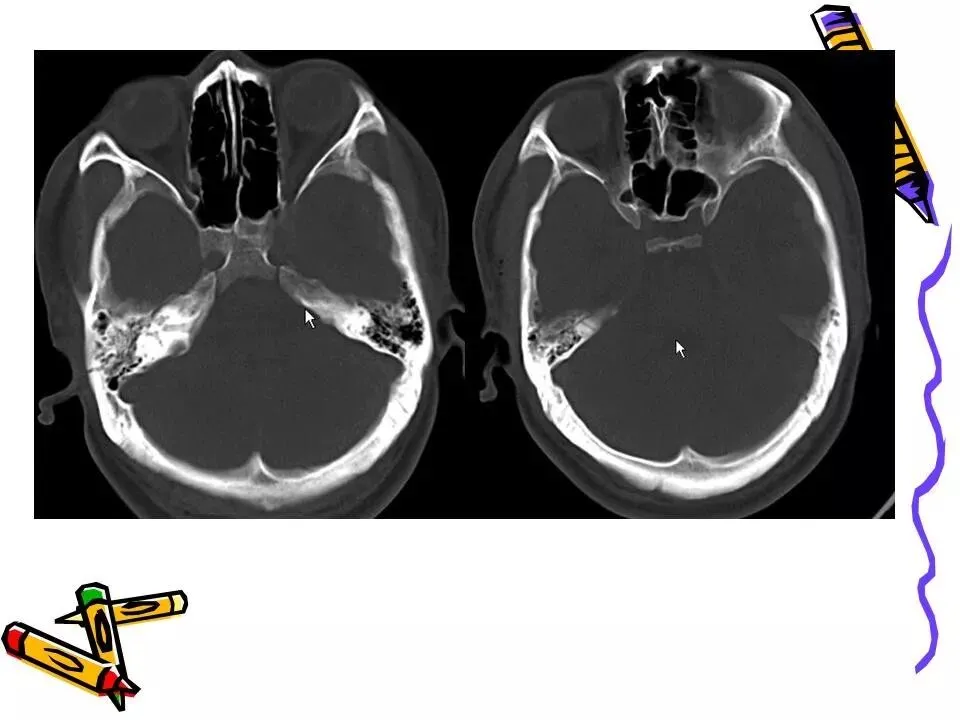

>常见颅脑外伤CT诊断(PPT)

常见颅脑外伤CT诊断(PPT)